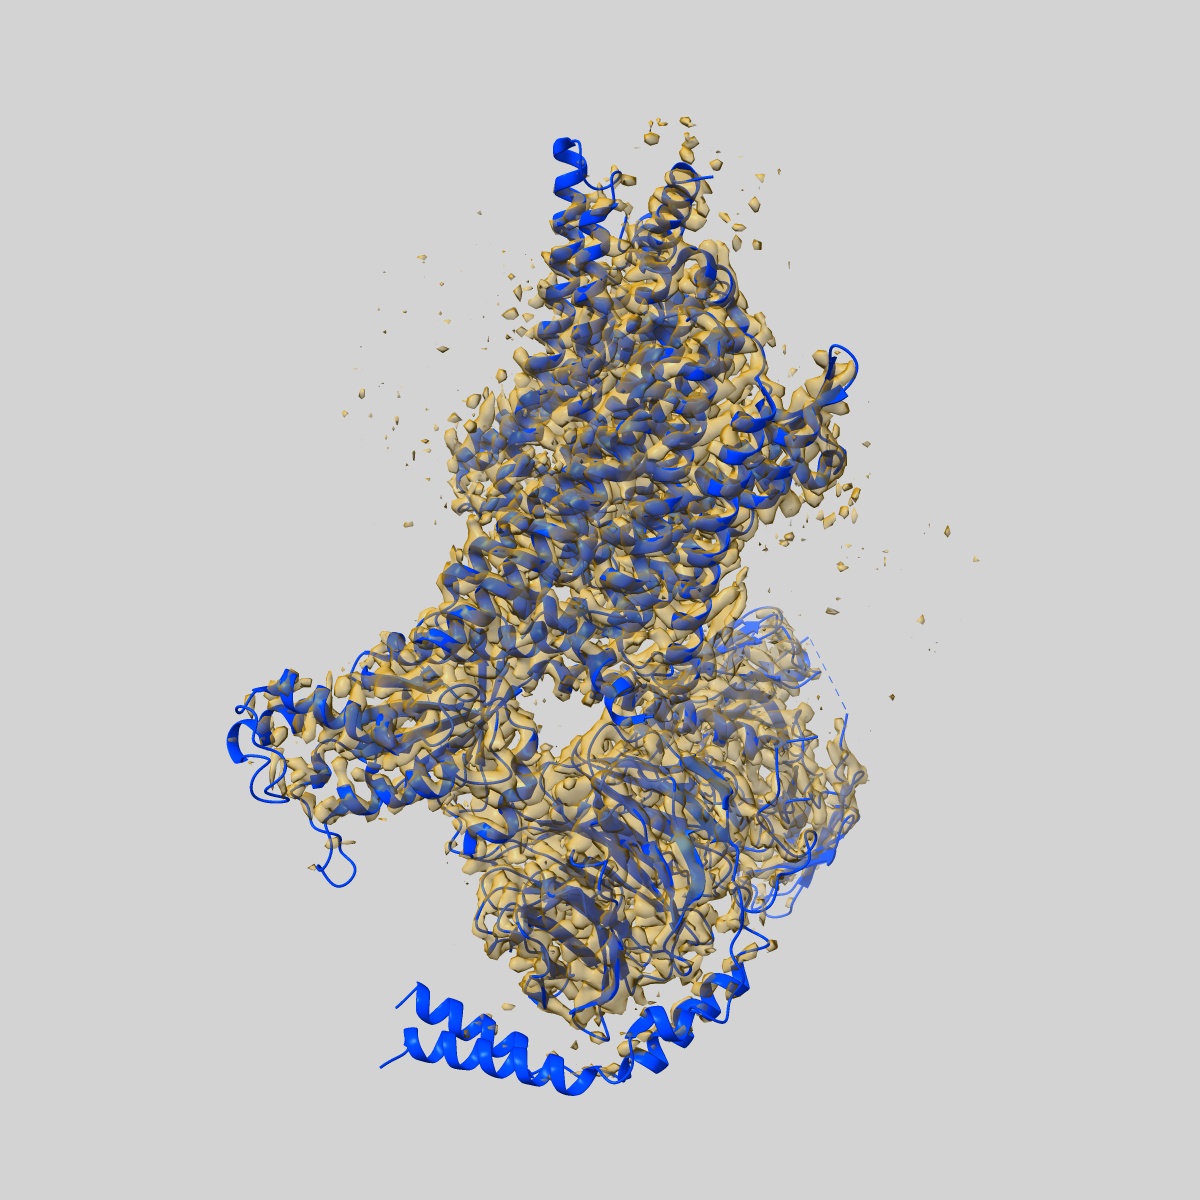

EMD-28069

Morphine-bound mu-opioid receptor-Gi complex

Single-particle3.2 Å

Sample: fentanyl bound mu-opioid receptor-G protein complex

Fitted models: 8ef6

Molecular recognition of morphine and fentanyl by the human mu-opioid receptor.

(2022) Cell , 185 , 4361 - 4375.e19